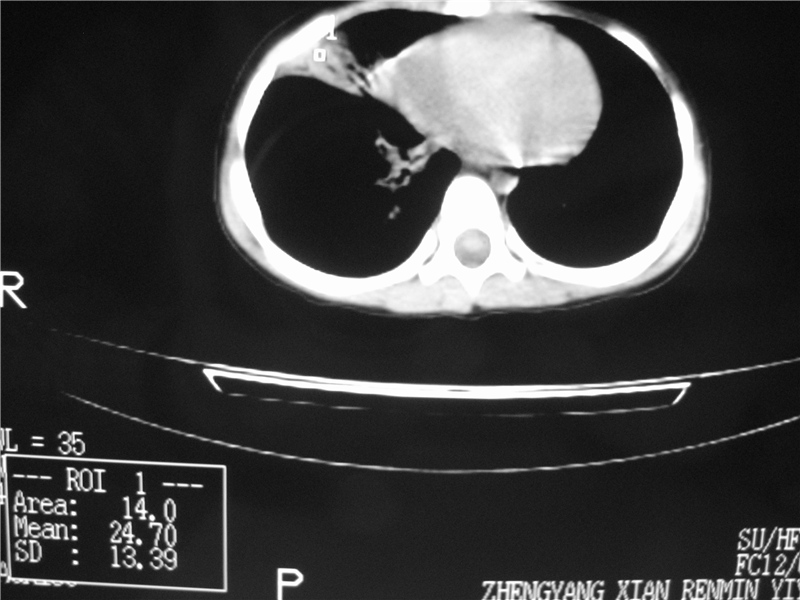

右侧中间段支气管阴性异物可能,建议支气管镜

1)右肺炎症并右肺中叶肺不张,右肺上叶充气不良。2)右侧支气管异物不排除。

结合病史,考虑气管异物所致。

再有,我们16排ct有气管重建功能,肯异物效果可以。